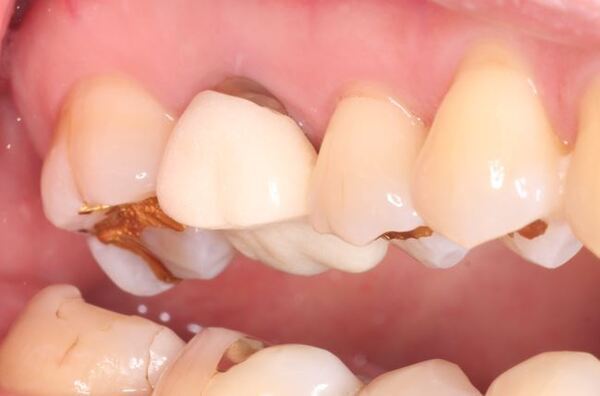

術前のデンタルX線写真と口腔内写真です。左下の一番奥の歯(#37)です。

左下の親知らずは1ヵ月ほど前に抜いたそうです。

親知らずと隣り合っていた歯の後ろ側(遠心)から虫歯が進行しています。